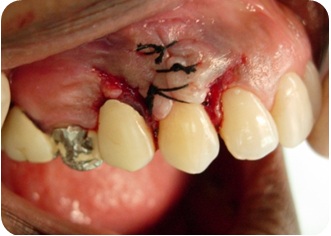

- Figura 3 (Português (Brasil))